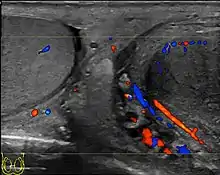

- Ultrasound scanning

- Lefort C, Thoumas D, Badachi Y, et al. (July 2001). "Orchites ischémiques: À propos de 5 cas diagnostiqués en écho-Doppler couleur" [Ischemic orchiditis: review of 5 cases diagnosed by color Doppler ultrasonography]. Journal de Radiologie (in French). 82 (7): 839–42. PMID 11507447. INIST 1080037.